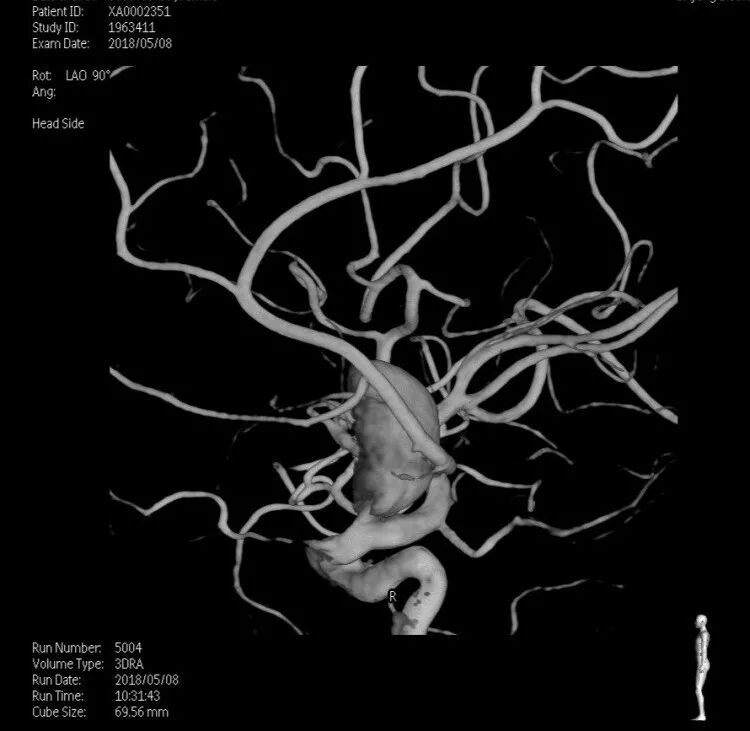

入院后完善DSA检查提示颅内多发动脉瘤:右侧颈内动脉眼段大动脉瘤(约18*19mm,瘤颈6.6mm),左侧眼动脉段及床突段动脉瘤。和家属沟通病情,告知介入和开颅手术风险利弊后,患者家属选择开颅动脉瘤夹闭手术治疗。进一步行DSA+CT融合,模拟手术入路视角。

术前融合后模拟开颅骨窗

术前融合后模拟显微镜视角

术前科室讨论:根据患者术前DSA+CT融合图像,左侧动脉瘤因右侧巨大动脉瘤及骨性结构的遮挡,无法手术夹闭。拟先行右侧动脉瘤夹闭。但右侧动脉瘤体型巨大,位于眼段床突旁,临近颅底,术中需要磨除床突,但可能诱发瘤体破裂,若无法有效阻断血流,极可能出现致死性出血。可考虑术前暴露颈总动脉分叉部,术中临时夹阻断颈内动脉,但增加了手术创伤。建议利用复合手术室优势,术中介入球囊临时阻断颈内动脉后行动脉瘤夹闭。

结合本病例,我们术前利用复合手术室飞利浦DSA血管机,造影后即刻行CT扫描。由于是在同一机器环境下完成的两种模态扫描,减少了伪影干扰,解剖结构电脑自动吻合,故影像融合精度极高。并且因为是双模态融合,可以用不同颜色标记血管和骨窗,增加了对比度,提高了分辨率,较CTA有明显优势。利用术前融合模拟手术入路,放大后观察发现动脉瘤体巨大,紧贴颅底和床突,缺乏至少2mm的近端阻断空间,术中需要磨除前床突。但术中发现动脉瘤表面张力极高,紧贴床突硬脑膜,高速磨钻操作存在巨大风险。而术中球囊阻断颈内动脉后,动脉瘤张力明显下降,依靠吸引器轻轻牵拉即可暴露出瘤颈,不必要磨除床突,降低了手术复杂度。